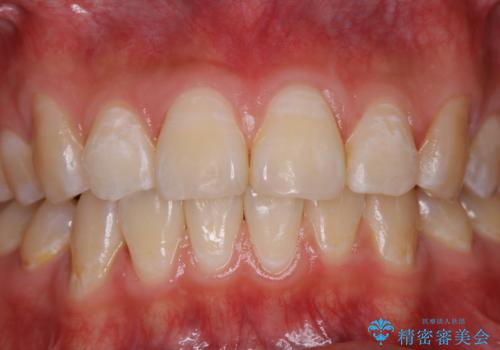

- 定期健診で全体的のチェックとクリーニング希望で来院されました。PMTC30分コースでクリーニングを行いました。

PMTCとは「Professional Mechanical Tooth Cleaning」の略で、専用の機器を使った歯のクリーニングです。

審美的面だけではなく、歯周病や虫歯・口臭などのリスクを予防することができます。

汚れを除去することにより、症状の早期発見につながります。